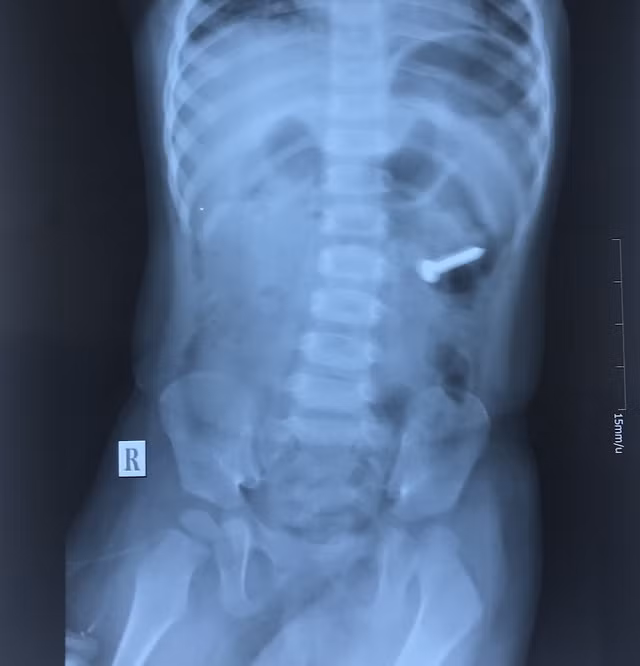

Bác sĩ Phùng Thị Hằng - Trưởng khoa Nội, bệnh viện Quốc tế Vinh, người trực tiếp tiến hành thủ thuật cho biết: “Sau khi đặt máy, xác định dị vật xuống sâu hơn ở D3 tá tràng so với phim X - Quang, cùng với đó dị vật có bề mặt xoắn ốc lại dài 3cm so với kích thước lồng ruột của trẻ 2 tuổi nên thủ thuật tiến hành rất khó khăn.”

Tuy nhiên, sau 30 phút dị vật đã được lấy ra qua đường nội soi. Kết quả kiểm tra lại niêm mạc tá tràng - dạ dày - thực quản không tổn thương, không chảy máu.

"Những trường hợp nuốt phải dị vật kim loại nhất là những dị vật có kích thước lớn rất nguy hiểm vì có thể làm thủng đường tiêu hóa gây áp xe trung thất hoặc viêm phúc mạc. Việc nội soi lấy dị vật cũng rất khó khăn có thể thất bại phải chấp nhận cuộc phẫu thuật”, Bác sĩ Phùng Thị Hằng cho biết.